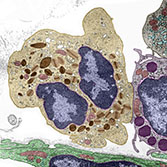

Histology is the study of the microanatomy of cells, tissues, and organs as seen through a microscope. It examines the correlation between structure and function.

Histology Guide teaches the visual art of recognizing the structure of cells and tissues and understanding how this is determined by their function. Rather than reproducing information found in a histology textbook, a user is shown how to apply this knowledge to interpret cells and tissues as viewed through a microscope.

An Aperio slide scanner was used to obtain a high-resolution image of each slide in its entirety. Large tissues are up to 34 GB for a single, uncompressed image of 150,000 x 75,000 pixels.

The contrast, color, and sharpness of each image were adjusted to at least maintain the appearance of the tissue as seen through a microscope. In many cases, these adjustments improved upon their visual appearance.

Unlike low-resolution images, users can interactively explore these large images by zooming-and-panning in real-time. A software-based virtual microscope (Zoomify HTML5 Enterprise) allows the examination of large and small structures in the same specimen.